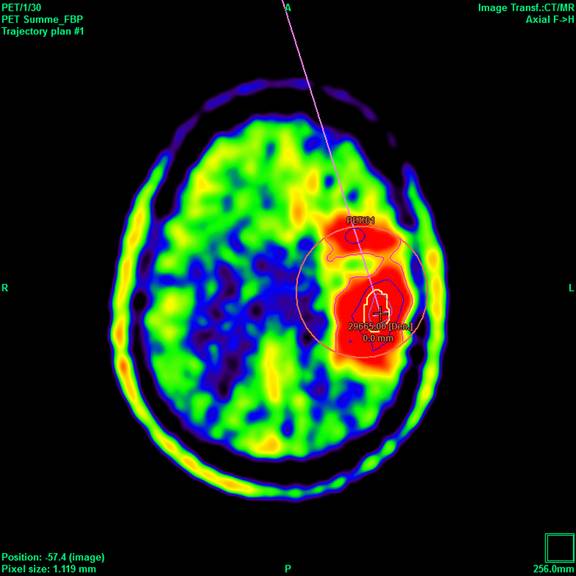

Die hohe Qualität der Bilddarstellung zeichnet das inomed Planning System (iPS) aus. Die automatische Zusammenführung verschiedener Bildmodalitäten ermöglicht eine schnelle und sichere Verifikation der geplanten Zugänge. Diese Zugänge sind für eine erfolgreiche THS zwingend notwendig. Auf Wunsch lassen sich anatomische Atlanten über patientenbezogene Daten projizieren. Dies erlaubt wiederum die Verifikation anhand anatomischer Grundlagen.

Die Planungssoftware iPS von inomed unterstützt sämtliche Planungsansätze, ob „freehand“, funktionell, atlasbasiert oder metabolisch orientiert. Hierfür stehen jeweils verschiedene Möglichkeiten zur Verfügung, die einander ergänzen können. Auch die Option einer Vorabplanung mit Übertragung auf die stereotaktische Bildmodalität gewährleistet die rasche aber genaue Zielpunktplanung am Tag des Eingriffs (THS, Biopsie etc.).

Ein leistungsstarker mehrstufiger Fusions-Algorithmus ermöglicht das Zusammenführen digitaler Bildinformationen, wobei immer der Erhalt der exakten Patienten-Geometrie im Vordergrund steht, bei gleichzeitiger Optimierung von anatomischer Sichtbarkeit und Bildqualität. Dies bildet die Grundlage für sichere Hochrisiko-Eingriffe wie der THS oder stereotaktisch geführter Biopsien.

- Unterstützt werden Bilder von CT, MRT, PET und Röntgen